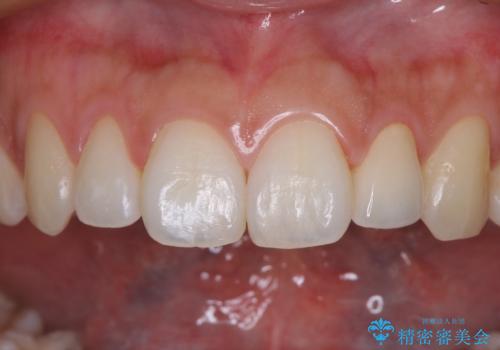

根管治療後速やかに痛みが消退し、6ヶ月後のレントゲン写真では、根尖部の病変がほぼなくなっていることが分かりました。